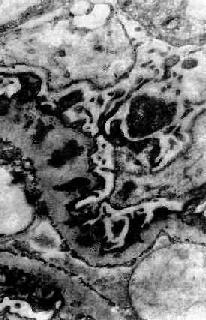

图12-18 膜性肾小球肾炎

电镜下见肾小球毛细血管基底膜表面,上皮细胞下电子致密沉积物,基底膜向表面突出伸入沉积物之间,上皮细胞足突融合